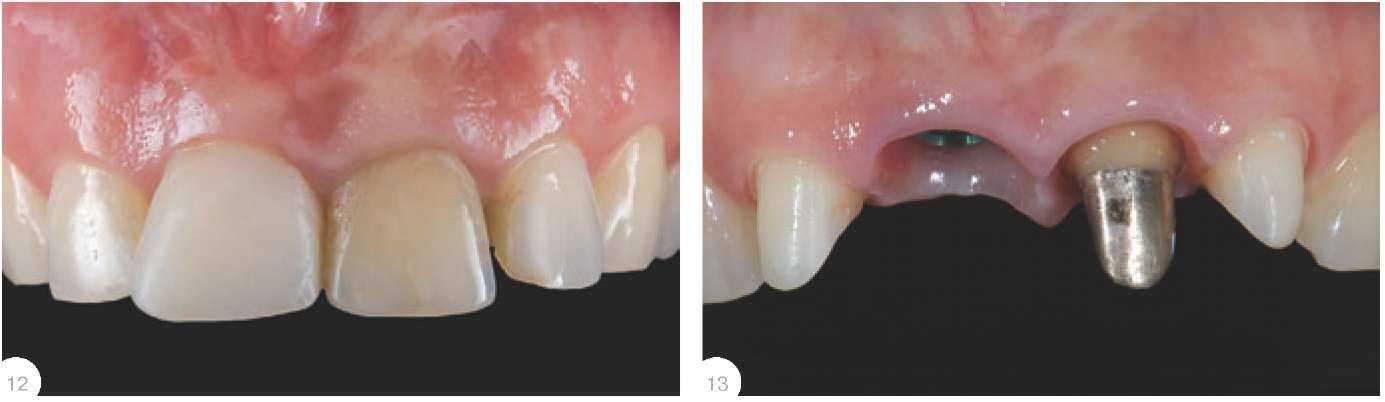

Винтовая фиксация Коронки с винтовой фиксацией могут быть изготовлены как прямым методом непосредственно врачом в клинике во время приема пациента, так и лабораторным путем. Умение применять прямой методявляется необходимым инструментом в арсенале ортопеда, который можно применить либо всилу удаленности лаборатории отклиники, либо в случае непредвиденного удаления и установки имплантата, и невозможности отпустить пациента без временной реставрации. К преимуществам прямого методанад лабораторным можно отнести возможность контроля необходимой поддержки мягких тканей впришеечной области, низкую себе стоимость, сроки.К недостаткам - не очень высокую либо вовсе низкую эстетику.Надо отметить, что применять метод винтовой фиксации стоит крайне осторожно. Следует ограничить количество откручиваний и прикручиваний таких коронок, особенно при тонком биотипе десны,так как (особенно на плохо отполированных конструкциях) из-за возникающего ложного прикрепленияи постоянной травматизации возможны большие рецессии. Лабораторный метод подразумевает под собой снятие оттиска ипосле получения из лабораториигипсовой модели ремоделирование десневого края согласно необходимому эстетическому контуру (лабораторную методику см.ниже). После того, как акриловыекоронки готовы, врач выполняетанестезию в области имплантатови прикручивает их до наступленияишемии десны (обязателен RVGконтроль). Важно помнить, что данная конструкция должна оказывать давле-ние только на мягкие ткани. В случае такого давления на подлежа-щую кость всегда развиваетсямощнейший болевой синдром спродолжительным воспалением и,как следствие, серьезной рецессией (рис. 12-13). Срок ремоделировки тканей в полости рта занимает от 4 до 6 недель и при достаточном количестве прикрепленной десны всегдадемонстрирует стопроцентный результат, который заключается видеальной имитации естественного десневого края. Однако, еслипланируется также протезирование соседних с имплантатами зубов, врач-стоматолог обязан помнить, что, не погружая уступ поддесневую область с апроксимальных сторон на границе с имплантатами, он рискует потерять десневой сосочек вследствие отсутствия его поддержки.В качестве иллюстрации этих теоретических построений позволюсебе привести небольшой пример. *) Отдавая дань моде, многие врачи изготавливают сегодня коронки издиоксида циркония на витальные зубы во фронтальном отделе, забывая отолщине колпачка будущей реставрации - 0,5 мм! Естественно, что техник для достижения эстетических запросов пациентананесет еще как минимум 1 мм керамической массы, и такая толщинанеизбежно приведет к чрезмерному препарированию! В то же время, применение на витальных зубах прессованных либо полученных на огнеупорных моделях конструкций позволяет врачу поройсохранять до 2/3 эмали (!), что многократно улучшает прогноз выживае-мости выполненной работы. Клинический случай Пациентка 29 лет, 11- перелом внижней трети. После детального разбора ситуации в присутствии зубного техника(Дмитрий Никоненко) принято решение об удалении 11 с одномо-ментной установкой имплантата,временной коронкой с винтовойфиксацией и протезированием 4резцов через 6 месяцев. По истечении этого срока мы приступили к эндодонтическому лечению 21 и изготовлению культевойвкладки. Принято решение изготовить индивидуальный абатмент идве коронки на каркасах из диоксида циркония на зубы 11 и 21, а навитальные 12 и 22 - бескаркасныекоронки толщиной не более 0,5 мм!* (рис. 14-17). Несмотря на превосходную эпителизацию, перед фиксацией коронок необходимо уложить междуабатментом, зубами и десной